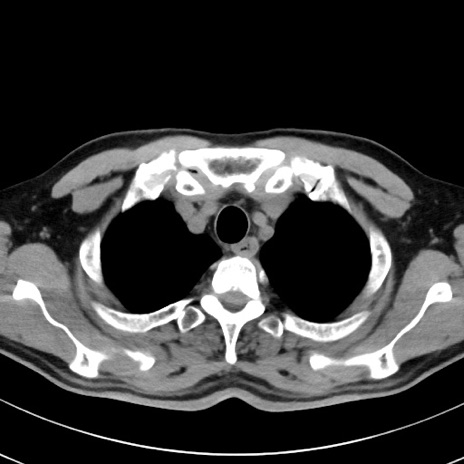

【腹部TIPS】症例29 参考症例 CT(横断像)

症例

70歳代男性